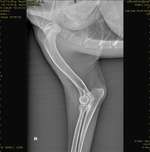

Unser kleiner Robby , Yorkischer Terrier, ist jetzt 7,5 Monate. Seid er ca.5 Monate jung war , denken wir befindet er sich im Zahnwechsel. Wir haben ihn mit 10 Wochen bekommen und seid dem 3.Tag bei uns schlief er komplett Nachts durch. Nach seinem 5.Monat hat er unruhige Nächte. Erst ...